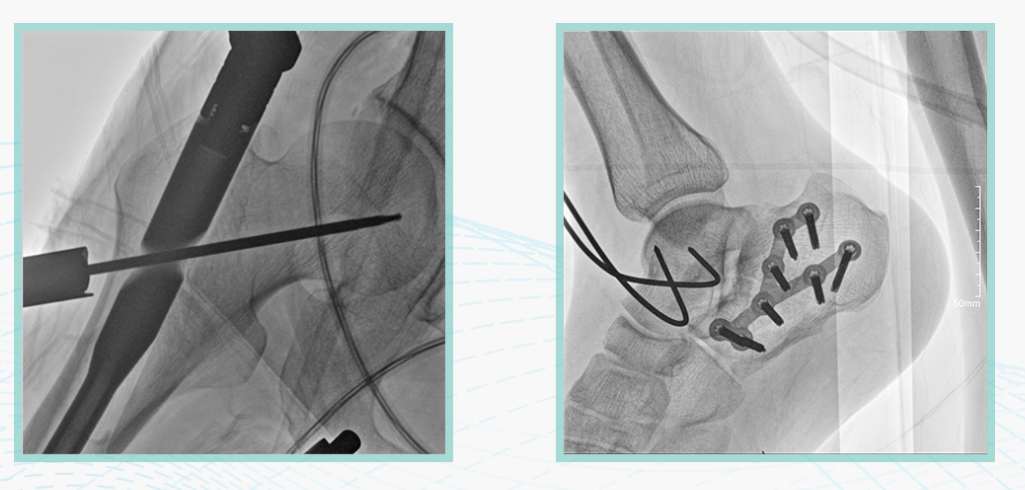

亿万28入口网页版-亿万28网页在线玩-万28官网下载最新版-亿万e网址pg-亿万28pg电子-亿万28赏金女王-亿万28娱乐科技悦画移动C臂X线摄影系统,采用了业内技术最尖端的CMOS探测器。基于性能优异的针状CSI闪烁体涂层和高灵敏度的CMOS感光芯片,悦画可以实现在超低X线剂量条件下实现高清晰影像成像,相较于一般的影增移动C臂和平板C臂,动态范围更高,影像的层次感和对比度更好。

在产品的性能参数设计上,悦画的像素可达到200万,空间分辨率可达到3.2线对,采用16bit的影像灰度,悦画在影像后处理上,通过SPI金字塔图像算法,支持摄影、脉冲透视影像、连续透视等多种模式下的影像采集,动态透视影像视频支持保存与回放。双大屏的设计,透视影像支持三档放大,保证临床影像读取的便利。

悦画在影像的伪影处理上,也积累多项图像处理专利技术。通过对植入物的精准识别,悦画能够精准祛除植入物伪影与运动伪影,保证高质量的影像输出,无论是影像的对比度、分辨率(清晰度)相较于市面上的移动C臂产品都更胜一筹。